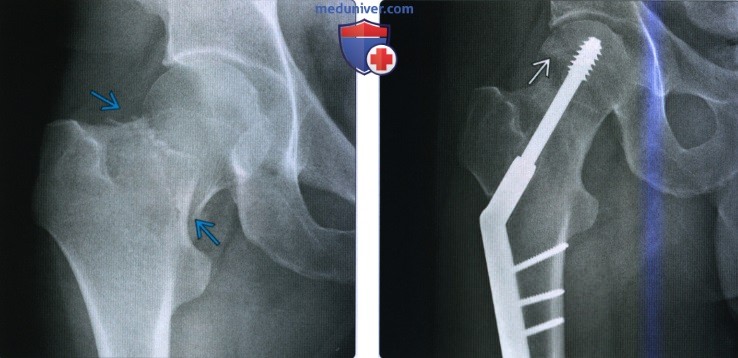

Классификация переломов диафиза бедренной кости: Иллюстрации и информация